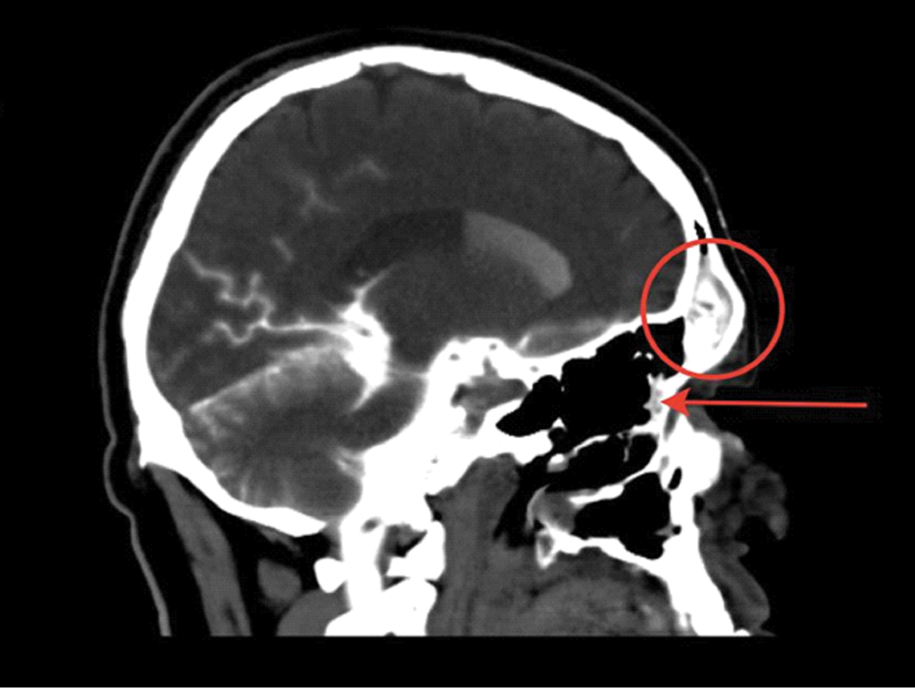

КТ-цистернография (КТ-Ц). При базальной ликворее применяются нейровизуализация ликворопроводящих путей с эндолюмбaльной инъекцией водорастворимых контрастных препаратов [12]. КТ-Ц дает возможность точно локализовать ликворную фистулу, выявить затекание контрастного препарата в придаточные пазухи носа и на основание черепа (рисунки 3, 4 и 5) [13, 34].

Рисунок 3. КТ-Ц с активной назальной ликвореей. Определяется распространение контрастного препарата из полости черепа в носовую полость через дефект основания черепа, в области продырявленной пластинки решетчатой кости слева дефект решетчатой кости обозначен стрелкой.

Рисунок 4. КТ-Ц с активной назальной ликвореей. Определяется дефект задней стенки лобной пазухи с пролабированием лобных долей (больше левой) в полость лобной пазухи – менингоэнцефалоцеле. В правой лобной пазухе визуализируется контрастный препарат, мигрирующий в полость носа. Желтая стрелка – менингоэнцефалоцеле; красный круг – контрастный препарат в правой лобной пазухе.

Рисунок 5. КТ-Ц с назальной ликвореей; красный круг – контрастный препарат в правой лобной пазухе; красная стрелка – контрастный препарат в полости носа.

КТ-Ц имеет до 96,7% вероятности выявляемости локализации ликворной фистулы при активной и 40% при неактивной ликворее. В остром периоде ЧМТ использование КТ-Ц имеет чувствительность до 56% в связи со сложностью дифференцировки между контрастным препаратом и геморрагическим субстратом в цистернах и в области передней черепной ямки [12, 31].